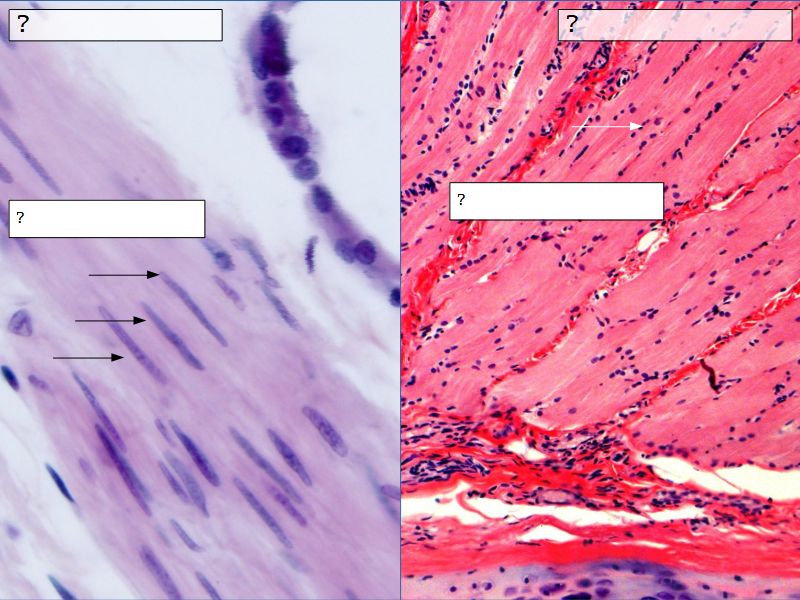

Fill in all the missing labels, and assess as you move through the slides. Answers on the down slide. It is important to do this using pen and paper, and not just glance through the images.